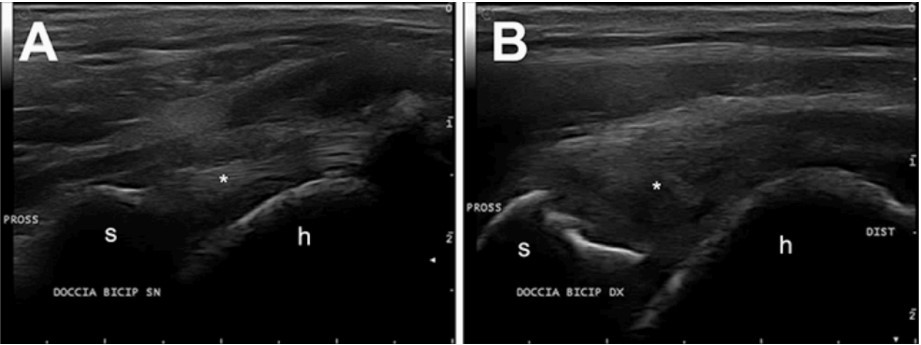

تقریباً 30 درصد از سگ های بالای 10 سال به این بیماری مبتلا می شوند که منجر به نارسایی میترال می شود. اکوکاردیوگرافی استاندارد طلایی برای ارزیابی ساختار و عملکرد قلب است و همراه با الکتروکاردیوگرافی و رادیوگرافی قفسه سینه به ابزار مهمی در ارزیابی می شود. پیشرفت بیماری را نشان می دهد و نشانه هایی را برای ارزیابی مناسب استراتژی های درمان پزشکی ارائه می دهد. سونوگرافی اسکلتی عضلانی یک زمینه به سرعت در حال رشد در دامپزشکی است. سونوگرافی برای اختلالات اسکلتی عضلانی معمولاً در پزشکی ورزشی اسب و طب انسانی استفاده می شود و امروزه به دلیل افزایش تشخیص آسیب های بافت نرم در بیماران حیوانات کوچک نیز بیشتر انجام می شود. مزایای سونوگرافی اسکلتی عضلانی در امکان کاوش است. همچنین اندام طرف مقابل، برای ارزیابی تقارن ساختارهای تاندون، و تکرار سونوگرافی برای ارزیابی روند بهبود. افزایش مسابقات ورزشی که خواستار قدرت بدنی هر چه بیشتر سگ ها است، منجر به افزایش آسیب های اسکلتی عضلانی شده است. بیماری های شانه شامل تاندون عضله دو سیپیتال به عنوان تاندونیت/پارگی جزئی (شکل 6)،عضله بالای خاری و عضله زیر خاری تحت تاثیر پارگی نسبی، و برداشتن استخوان انتهایی تاندون از شایع ترین آسیب های مشاهده شده است. میوزیت مزمن عضلات ایلئوپسوآس باید به عنوان یک بیماری معمولی در نتیجه مسابقات ورزشی سگ ذکر شود. در میان این بیماری ها سایر شرایط پاتولوژیک که می توان از نظر سونوگرافی در نظر گرفت شامل پارگی عضلات، نئوفرماسیون عضلانی (گرانولوم/آبسه/نئوپلازی)، استئوآرتریت و بیماری های تاندون/رباط (التهاب، پارگی جزئی/کامل) می باشد.

شکل6. پارگی تاندون عضله دوسر پروگزیمال راست در یک زن 4 ساله عقیم شده Deutsch Kurzhaar. اسکن طولی درج پروگزیمال تاندون چپ (الف) و راست (ب) عضله دوسر بازو. تاندون راست ساختار اکوی فیبریلار طبیعی قابل مشاهده در سمت چپ را از دست داد، این تاندون هیپواکویک با برخی نقص های کوچک آنکوییک است. S: نیمرخ های دیستال توبرکل گلنوئید کتف راست نامنظم است. h = سطح جمجمه پروگزیمال هومروس. * =تاندون عضله دوسر بازو.